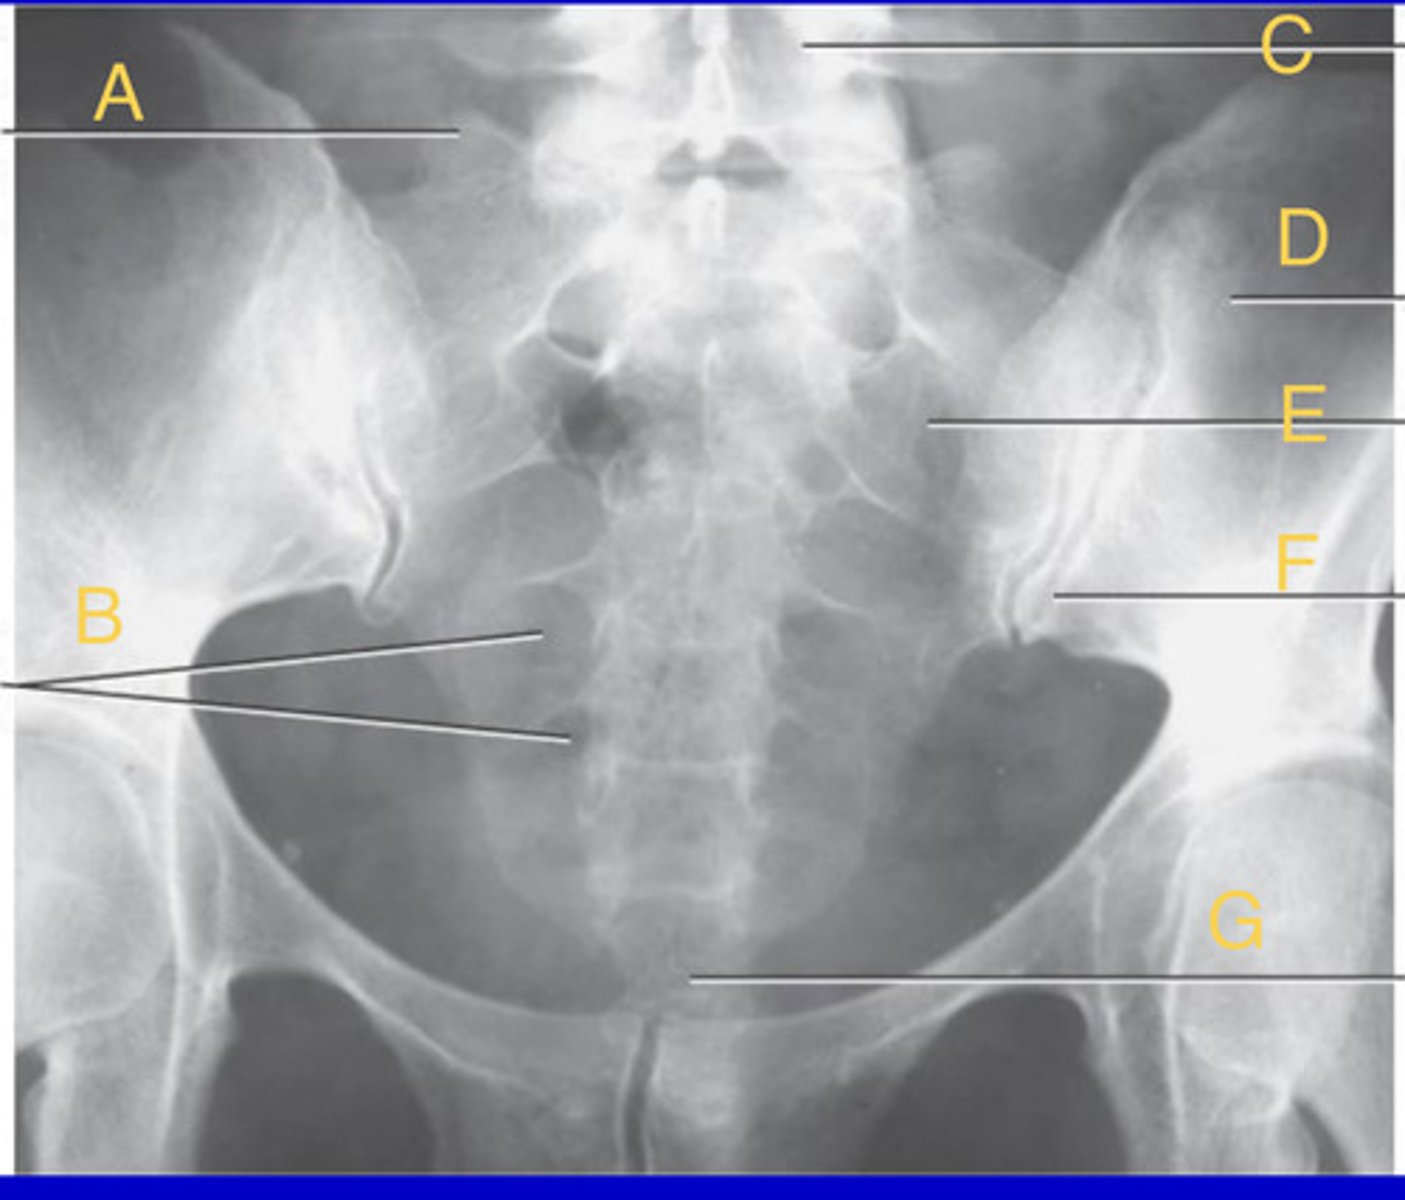

L2 body

A.

L3 transverse process

B.

L3-4 zygapophyseal joint

C.

L5, superior articular process

D.

L3 Pedicle

E.

L4 pars interarticularis

F.

L4 inferior articular process

G.

What position?

Oblique lumbar